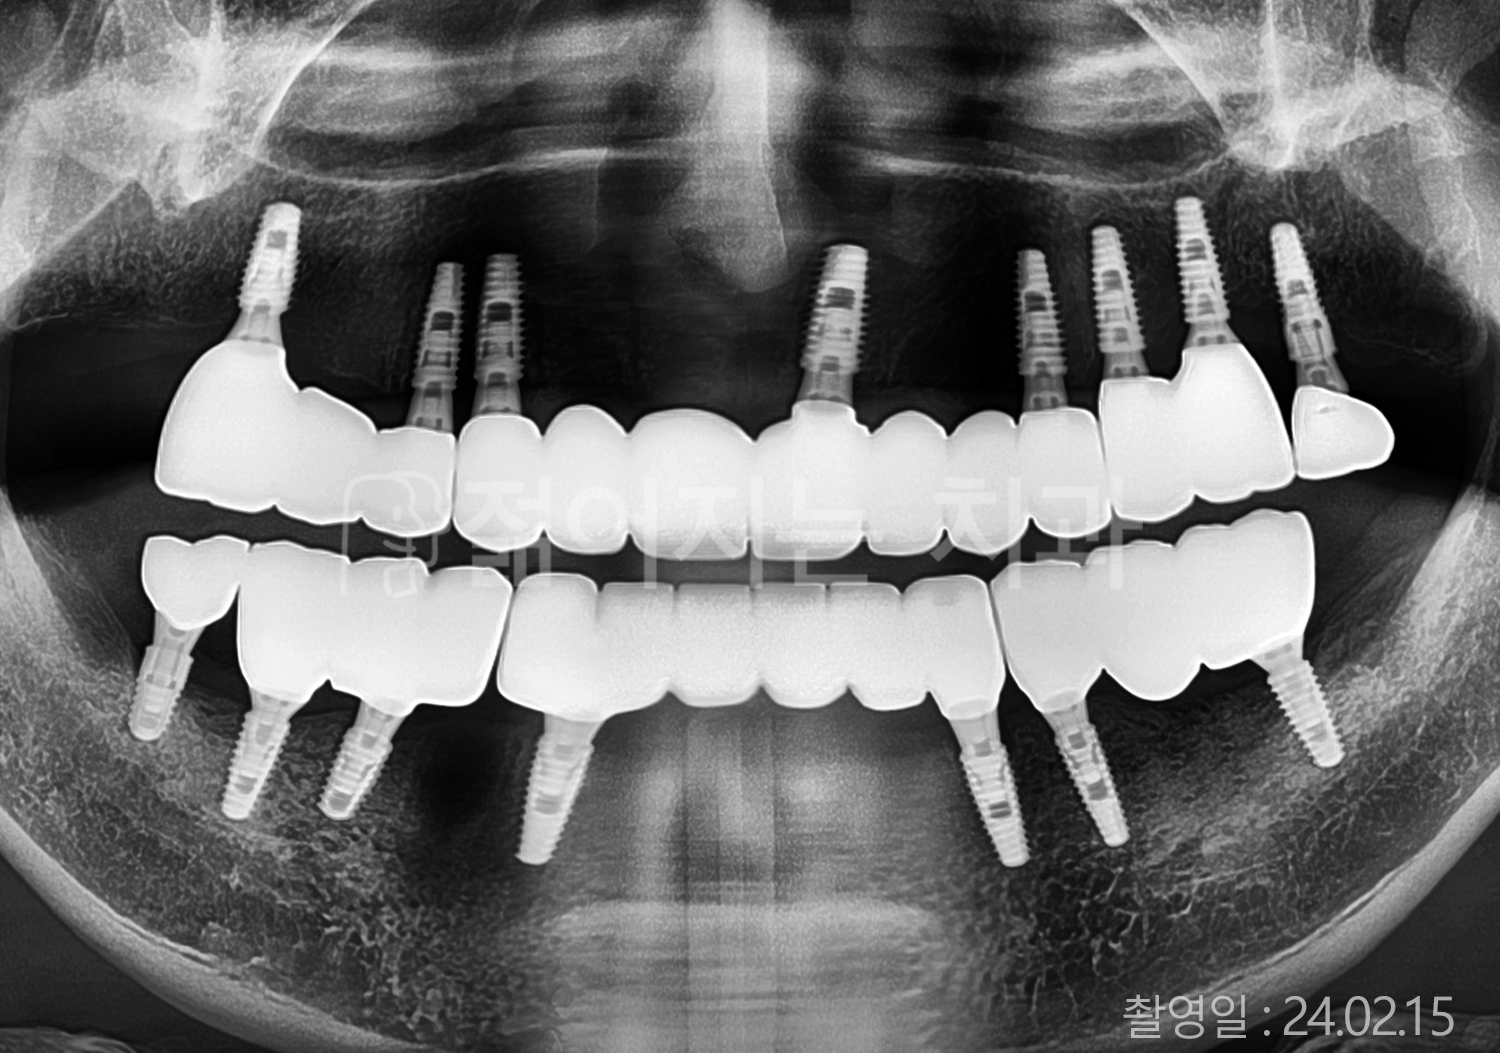

• 70대 고혈압, 고지혈증 전체치아 10개 이상 임플란트

• 60대 당뇨, 간염 전체치아 10개 이상 임플란트

• 80대 골다골증 전체치아 6개 이상 임플란트

• 70대 고혈압, 당뇨 전체치아 10개 이상 임플란트

• 60대 간 질환 전체치아 10개 이상 임플란트

• 60대 전체치아 10개 이상 임플란트

• 70대 전체치아 10개 이상 임플란트

• 50대 전체치아 10개 이상 임플란트

• 60대 고혈압, 고지혈증 전체치아 10개 이상 임플란트

• 40대 고지혈증, 뇌혈관 질환 전체치아 10개 이상 임플란트